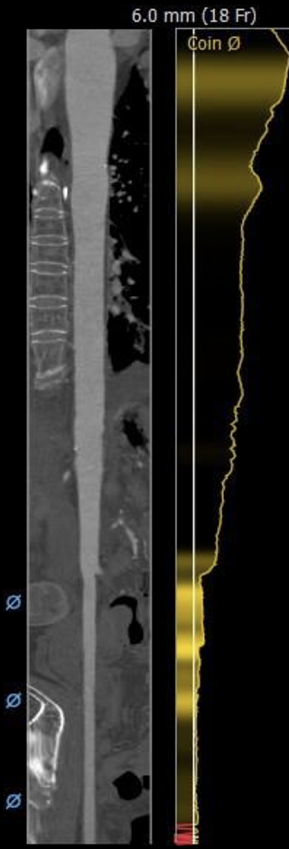

非横位心,主动脉弓角度与宽度合适。入路血管局部钙化,双侧血管内径良好,整体入路血管条件较好。

外周血管及主动脉弓解剖